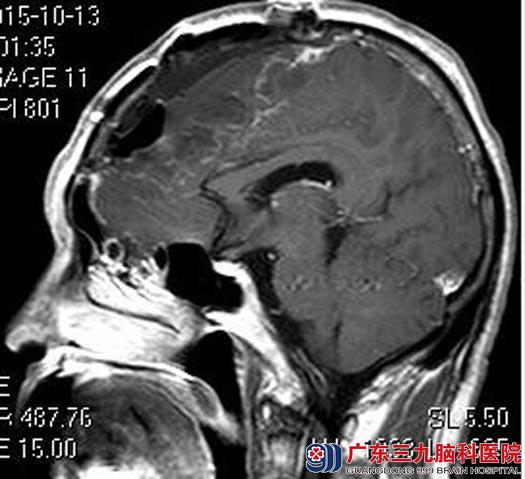

杨先生一年前因头痛在当地医院检查,发现脑肿瘤,在某三级医院行肿瘤切除术,术后病理检查提示脑膜瘤II级,未行放射治疗,也未按时复查。

术后一年,杨先生出现双下肢乏力;一月多月前行头颅MR检查提示肿瘤复发。没有及时复查及行进一步的放射治疗,导致肿瘤复发,家人都很自责。

广东三九脑科医院头颅MR检查提示:拟额部脑膜瘤术后复发,大小约6.24cm×4.54cm×8.54cm,邻近脑膜示线样明显强化,跨越中线向对侧生长,相应部位额骨受累及。